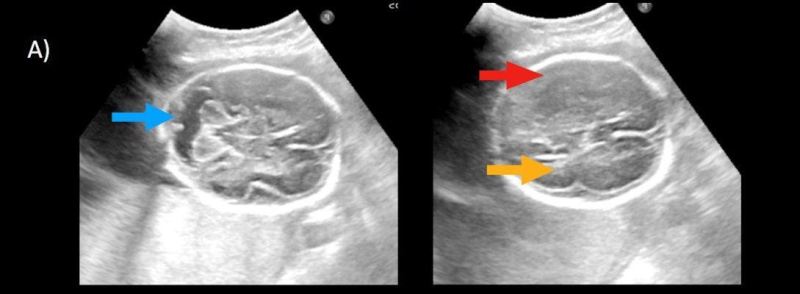

- B) Aksiyel ve sagittal T2A görüntülerde gyrus ve sulkuslarda azalma mevcut olup korteks kalınlaşmış görünümde ve operkulizasyon ayırt edilememiştir. Korteks beyaz cevher ayrımı zor seçilmektedir (ok) Ekstraaksiyel BOS mesafesi artmış görünümdedir (ok). Yapılan ölçümlerde; tegmentovermian açı :8 derece (ok) serebellar vermis boyutları kraniokaudal: 16 mm, aksiyel: 5,5×8,5 mm (ok) ölçülmüş olup BPD:27w ile uyumlu olan fetüste haftasıyla uygun olarak değerlendirilmiştir.